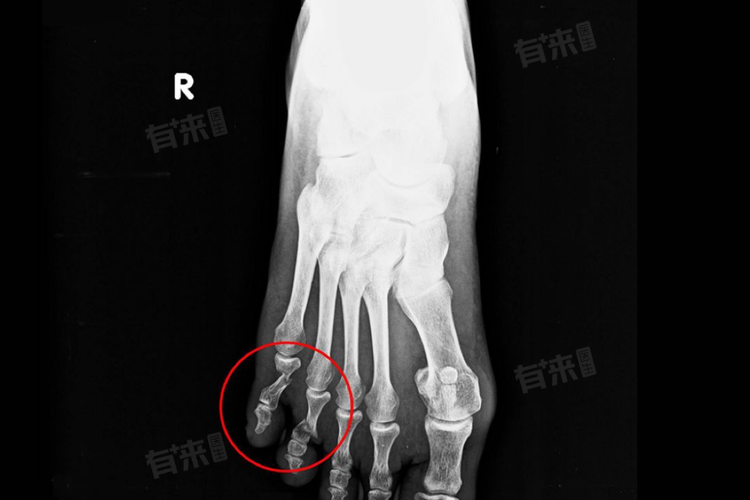

脚趾骨折15天就走路通常是不建议的。骨折后的2周内,骨折部位处于血肿机化演进期,此时周围的纤维组织虽然覆盖了骨折端,但这种软性组织并没有正常地束缚骨折端的能力。如果此时下地行走,容易导致骨折断端的移位。

- 一般来说,脚趾骨折后,需要得到有效的复位和固定。在脚趾骨折后的15天,骨折部位还处于愈合的早期阶段,骨痂尚未形成或形成不完全,骨折端的稳定性较差,此时走路会对骨折位置造成压力,可能导致骨折部位错位,影响骨折的正常愈合过程。

- 脚趾骨折在6-8周左右才能达到早期的愈合阶段,此时骨折处可能有骨痂形成,骨样组织覆盖于骨折端。这些骨痂具有一定的抗击肌腱旋转的能力,从而可以有效防止骨折移位。可以考虑拆除石膏并适当进行下地活动,但这并不意味着可以立即恢复正常行走,需在医生或康复治疗师的指导下逐步进行功能锻炼,以恢复脚趾的功能和灵活性。